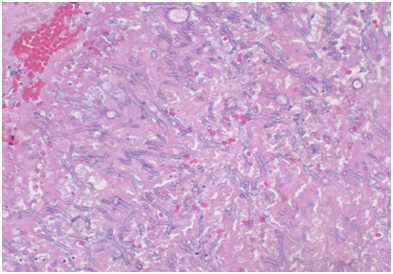

A 57-year-old white male patient with known history of coronary artery disease, morbid obesity, obstructive sleep apnea, hypertension, hyperlipidemia, atrial fibrillation, and tobacco use, presented to a local emergency room with a sudden sharp right arm pain, followed a few hours later by numbness of the right hand. His physical exam was normal except for a very weak pulsation of the right brachial artery. His initial workup included a normal chest x-ray with no acute cardiopulmonary process. A doppler ultrasound of the right upper extremity indicated thrombosis with near-complete occlusion of the distal right brachial artery. He was urgently seen by vascular surgery and underwent thrombectomy of the distal right brachial artery thrombus that was sent for pathology. Hematoxylin Eosin stain and Grocott’s methenamine silver stain showed fungal organisms identified at the thrombus, that had thin septate hyphae with regular branching and that were morphologically consistent with Aspergillus species (Figures 1-6). Subsequently, he was started on intravenous voriconazole, after his EKG, liver function tests were evaluated revealing a normal QTc interval, and liver enzymes respectively. Patient was then evaluated for evidence of disseminated Aspergillosis. His blood cultures have been negative. Aspergillus galactomannan antigen was negative, and his HIV ½ Antibody screen was negative. A computed tomography (CT) scan of the chest with angiography showed an ascending aortic pseudoaneurysm with large soft tissue component, representing a mycotic aneurysm. The contrast opacified lumen of the pseudoaneurysm measured 2.8 x 3.8 cm and there was a portion of the pseudoaneurysm more superiorly that was thrombosed measuring 6.3 x 7.2 cm (Figures 7 & 8). His lungs were clear without evidence of pulmonary nodules or consolidation. CT scan of the brain with contrast and a complete ophthalmological examination were unremarkable. Transthoracic and transesophageal echocardiograms showed no major cardiac finding and no evidence of valvular vegetations. He was then transferred to a tertiary care center where he underwent a homograft of cryopreserved human tissue given the fact that he has an infected mediastinum. He was continued on Voriconazole orally, and he will receive it for life.To note that, five years prior to this event, he underwent an urgent coronary artery bypass grafting (CABG)X3 with reversed autogenous saphenous vein graft from the aorta to the left anterior descending artery, from the aorta to the ramus intermediate, from the aorta to the obtuse marginal artery, along with endoscopic vein harvest left and right greater saphenous veins (from knee to groin bilaterally).

Figures 1-3 Hematoxylin-Eosin stain showing thin septate hyphae with regular branching.